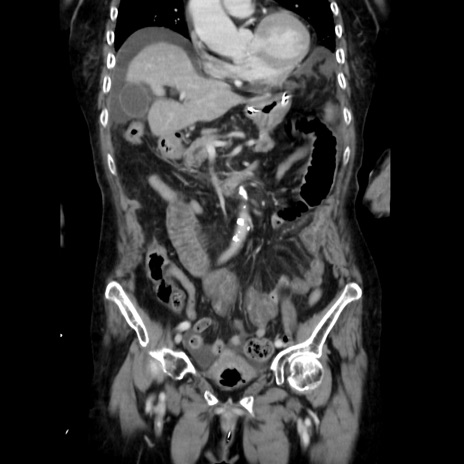

症例40(冠状断像)

【症例】90歳代女性

【主訴】腹痛・嘔吐

【現病歴】 食欲低下、嘔吐があり昨日他院受診。肺炎と診断され入院となる。入院後より腹部全体に圧痛あり。胃管留置され経過みていたが、症状持続するため、

当院転院となる。

【既往歴】胸椎圧迫骨折、胆石症

【身体所見】腹部:中央に激痛あり、圧痛あり、反跳痛不明

【データ】WBC 17100、CRP 18.82

冠状断像